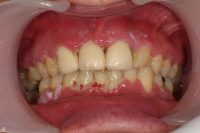

Förekomst av gingivala hyperplasier med djupa tandköttsfickor och svåra hygienförhållanden som följd.

Läkemedelsinducerad gingival hyperplasi:

En volymökning av mjukvävnaden kring tänderna som är associerad med intag av läkemedel tillhörande grupperna antiepileptika, immunosuppressiva läkemedel och kalciumblockerare.

Inflammation är den utlösande faktorn som driver tillväxten av mjukvävnaden därför är plackkontroll av största vikt.